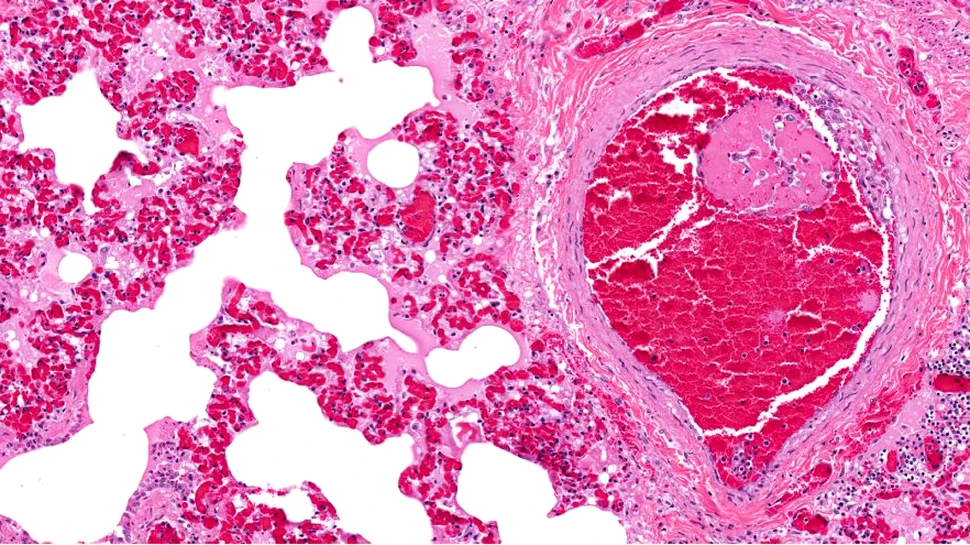

Cercetătorii au examinat mostre de țesut ale inimii de la pacienți care au murit la începutul pandemiei de COVID-19. Au fost găsite cheaguri de sânge frecvente și extinse (semnele trombozei cardiace) în vasele inimii, așa cum era anticipat, dar tipul de modificări ale celulelor endoteliale care căptușesc inima, care sunt de obicei observate în tromboze, au fost absente.

În schimb, datele au indicat că un posibil vinovat este hipercoagulabilitatea sângelui cauzată de neutrofilele activate, un tip de globule albe. Descoperirile lor sunt publicate în revista The American Journal of Pathology.

Tromboza a fost cea mai frecventă constatare patologică în grupul COVID-19, cu o frecvență foarte crescută a microtrombusurilor și a numărului total de macrotrombusuri în comparație cu martorii negativi pentru COVID-19.

Cercetătorii nu au reușit să găsească astfel de modificări endoteliale la locurile de tromboză. În schimb, au văzut că trombusurile cardiace la patru dintre cei șase pacienți cu COVID-19 conțineau neutrofile care exprimau modificări procoagulante în sânge, cum ar fi citrulinarea histonelor asociată cu formarea de capcane extracelulare pentru neutrofile (NET).

Unele imagini sugerează că NET par a fi direct asociate cu trombocitele. Macrotrombusuri bogate în neutrofile, compuse din 30% sau mai multe neutrofile au fost găsite frecvent în grupul COVID-19, dar nu și în probele de țesut de control.